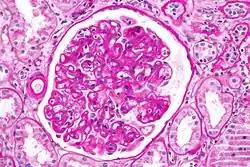

| Micrograph showing lung transplant rejection. Lung biopsy. H&E stain. | |

Diagnosis of acute rejection relies on clinical data—patient signs and symptoms but also calls on laboratory data such as blood or even tissue biopsy. The laboratory pathologist generally seeks three main histological signs: (1) infiltrating T cells, perhaps accompanied by infiltrating eosinophils, plasma cells, and neutrophils, particularly in telltale ratios, (2) structural compromise of tissue anatomy, varying by tissue type transplanted, and (3) injury to blood vessels. Tissue biopsy is restricted, however, by sampling limitations and risks/complications of the invasive procedure.[31][32][33] Cellular magnetic resonance imaging (MRI) of immune cells radiolabeled in vivo might—similarly to Gene Expression Profiling (GEP)—offer noninvasive testing.[34][35]